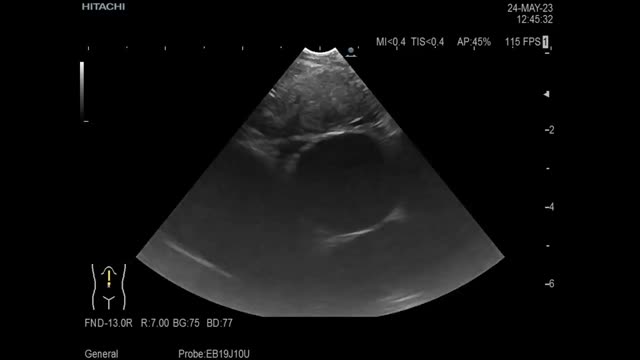

We report the case of a 67-year-old man admitted to our hospital due to respiratory failure and weight loss. Chest CT showed a 4cm right upper lobe mass, an enlarged subcarinal lymph node and liver metastases (Fig. 1a). As performing a conventional EBUS posed a high risk due to the patient's respiratory failure, we decided to take the esophageal route (EUS-B) with the aim of obtaining a histological sample for molecular and immunohistochemical analysis using a 1.1mm cryo-probe (Erbecryo 20402-401, Tubingen, Germany). The station 7 lymph node was localized by EUS-B and a fine needle aspiration (FNA) was performed using a 22-G needle (SonoTip TopGain; Medi-Globe, Rohrdorf, Germany) (Fig. 1b). We created a pathway (tunnel) from outside the lymph node by shortening the length of the needle, with the aim of breaking the mucosa, submucosa and finally the lymph node capsule, to allow the passage of the cryo-probe into the lymph node to perform the cryobiopsies (Fig. 1c–e). Once the lymph node capsule was broken (Fig. 1f), the cryoprobe was introduced gently under ultrasound guidance (Fig. 1g); once inside the lymph node and positioned in the desired area, the cryo-probe was frozen for 5s and the EBUS scope and the cryo-probe were taken out as a whole with no complications (Fig. 1h). The puncture sample was suspicious for non-small cell carcinoma due to the significant degree of necrosis present, however, the cryobiopsy sample was optimal to issue a definitive diagnosis (squamous cell lung carcinoma) (Fig. 1i) and perform the necessary molecular and immunohistochemical studies with an estimated tumour cellularity greater than 70% (negative EGFR, PD-L1 <50%, negative for ALK and ROS-1). During the patient follow-up there were no complications associated with the technique (no pneumothorax, no hemoptysis, no pneumomediastinum, no data of infection). Huang et al. published a case report in which they performed a transesophageal cryobiopsy to diagnose Hodgkin's lymphoma. In their procedure, the esophageal wall was first cut with a needle knife prior to introducing the cryo-probe,1 unlike our method, where we only use the 22-G needle.

(a) CT showing an enlarged subcarinal lymph node localized by EUS-B. (b) EUS-B image showing the 22-G needle (SonoTip TopGain; Medi-Globe) inside the lymph node. (c–e) We perform 10–12 passes shortening from distally to proximal the length of the needle to create a pathway with the aim of breaking the mucosa, submucosa, and the lymph node capsule. (f) Broken lymph node capsule prior to introduce the 1.1mm cryo-probe (Erbecryo 20402-401). (g) EUS-B image showing the tip of the 1.1mm cryo-probe within the lymph node. (h) Pentax EBUS scope (EB-1970UK) with 1.1mm cryo-probe in the working channel. The tip of the probe has the lymph node tissue obtained by cryobiopsy. (i) Microscopic image of cryobiopsy (10×) showing a well-preserved architecture compatible with squamous cell lung carcinoma.